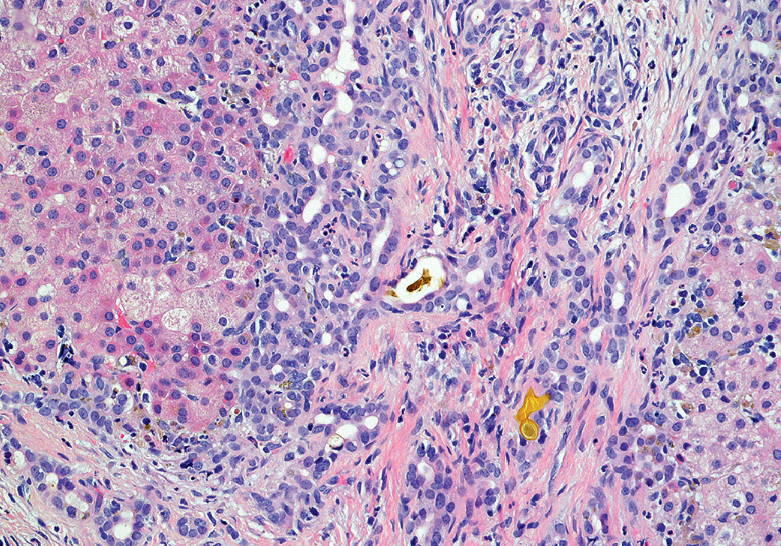

- Liver biopsy: Shows bile duct proliferation and fibrosis